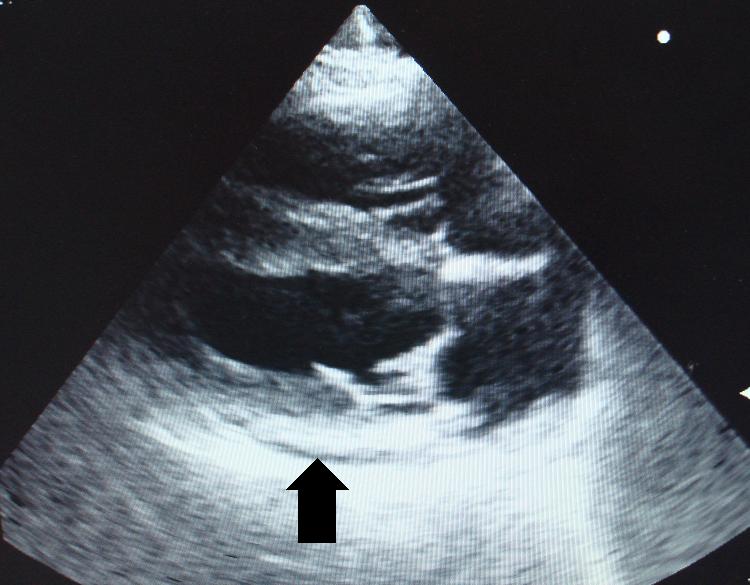

Po odsátí jsme opět sonograficky zkontrolovali srdce a osrdečník (černá šipka ukazuje na zbytek tekutiny, která v osrdečníkovém vaku po odsátí zůstala):

Echokardiografie-perikardiální efuze-stav po odsátí tekutiny